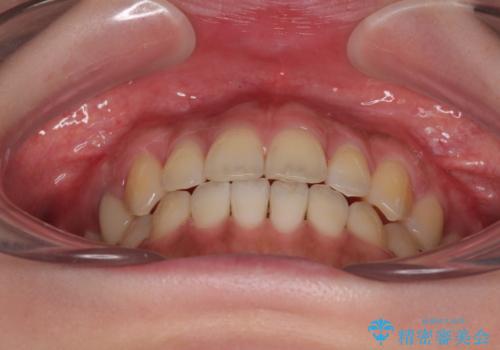

開咬をワイヤー装置で矯正治療

治療開始から8ヶ月ほどで遠方への転勤が決まりましたが、歯列は概ね整っていたため、その後は東京出張を狙って治療を終える処置を行うことができました。